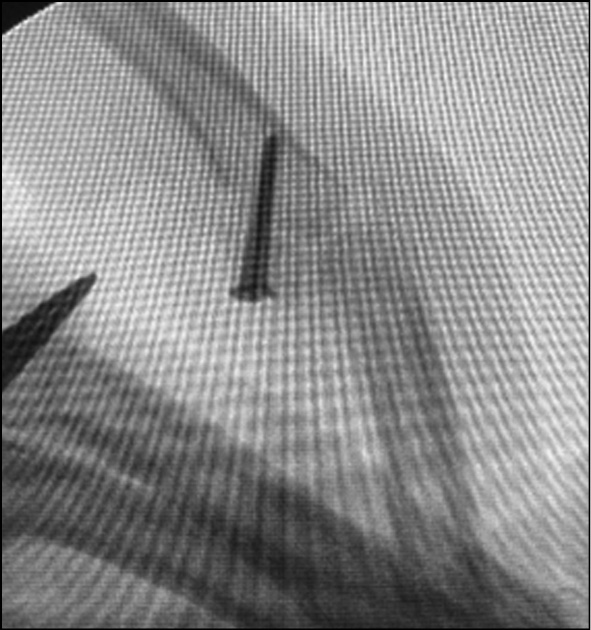

Fig. 6. X-ray control after fixation of the graft with screws.

Fig. 7. Intraoperative picture after fixation of the graft with screws.

A method of hemiarthroplasty from the hook bone of the hand for injury to the palmar edge of the base of the middle phalanx

The hand was placed on an extension table in the supine position, and a pneumatic cuff was applied. The surgical field was treated three times with antiseptic solutions. A trapezoidal incision was made along the palmar surface in the projection of the PIP joints of the injured finger with skin flap withdrawal. Access to the flexor tendon canal was realized. The latter was U-shapedly dissected in the gap between the annular ligaments A2 and A4, and the canal flap was bent. The tendons of the superficial and deep flexors are isolated and withdrawn. The palmar plate was distally cut from the scar tissue, along with a fragment of the improperly fused palmar edge of the base of the middle phalanx. The collateral ligaments were proximally cut from the head of the proximal phalanx. Dislocation of the PIP joints to the rear was performed, and scar tissue was excised. The area of damage to the articular surface of the palmar edge of the base of the middle phalanx was detected, and an economical resection of the damaged part of the phalanx was performed. Measurements of the middle phalanx defect were made. A separate linear skin incision was made along the dorsal surface of the hand in the area of the IV−V carpal–carpal (CMC) joint. The joint capsule was longitudinally dissected. The articulation of the hook bone with the bases of the IV−V metacarpal bones was identified. A tangential osteotomy of the dorsal surface of the metacarpal bases was performed using a chisel. Based on the size of the middle phalanx defect, a graft from the hook bone was marked and isolated. The graft was fixed to the phalanx with a bone holder, alternately drilled in the dorsal direction, and affixed with two 1.5 mm screws to the dorsal edge of the middle phalanx. The phalanx dislocation was repositioned and checked using an electron optical transducer (EOT). The positions of the phalanges and screws are confirmed to be correct. The capsule in the area of the CMC joint was sutured with passive drainage. The distal edge of the palmar plate and the proximal ends of the collateral ligaments are sutured together, harboring the screws. The flexor tendon capsule flap is passed under the tendons and sutured from the cutoff site. The skin flap is sutured with knotted sutures. An aseptic dressing is applied. Fixation in a posterior plaster cast bandage in the position of flexion in PIP joints at 30° (Figs. 1−8).